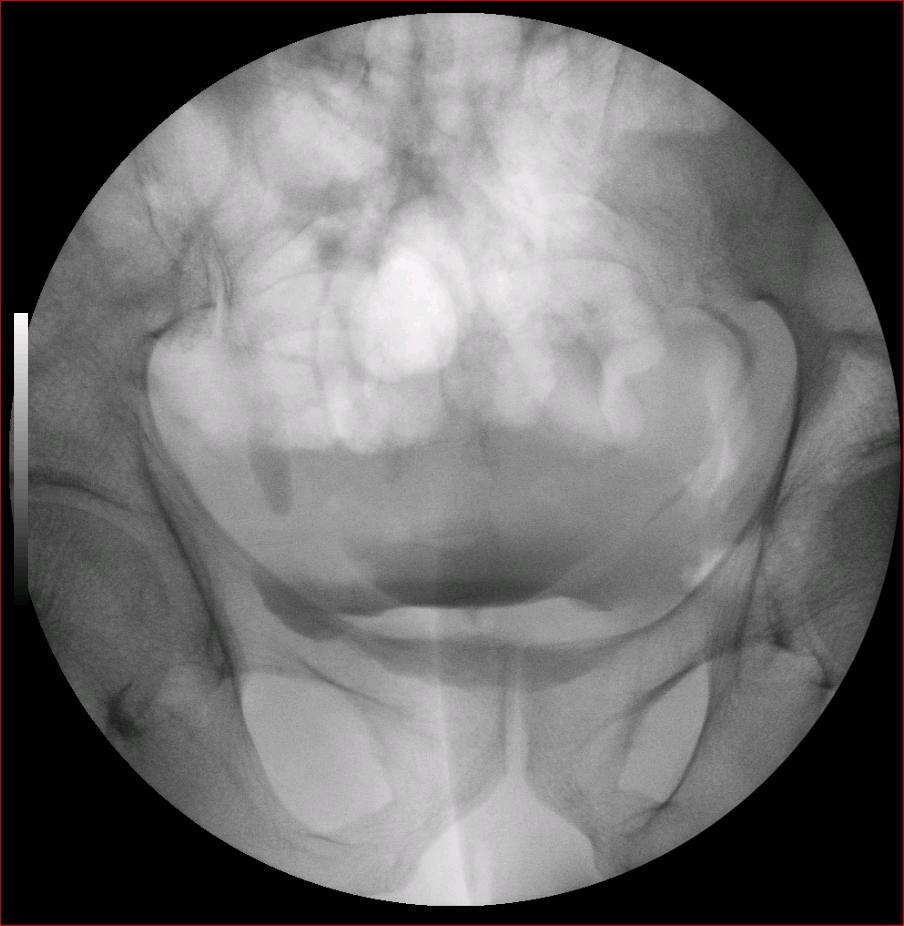

以下是引用luoxinjun在2008-2-18 15:54:00的发言:[br]右肾积水,右输尿管下端结石

以下是引用zhangxiangjun在2008-2-18 21:01:00的发言:[br]右输尿管盆段末端结石,继发其近端输尿管、右肾积水。

以下是引用hexue在2008-2-18 17:33:00的发言:[br]右输尿管下段结石并右肾及右输尿管积水扩张

以下是引用杀毒软件在2008-2-18 16:24:00的发言:[br]右输尿管下段结石,肾盂积水。